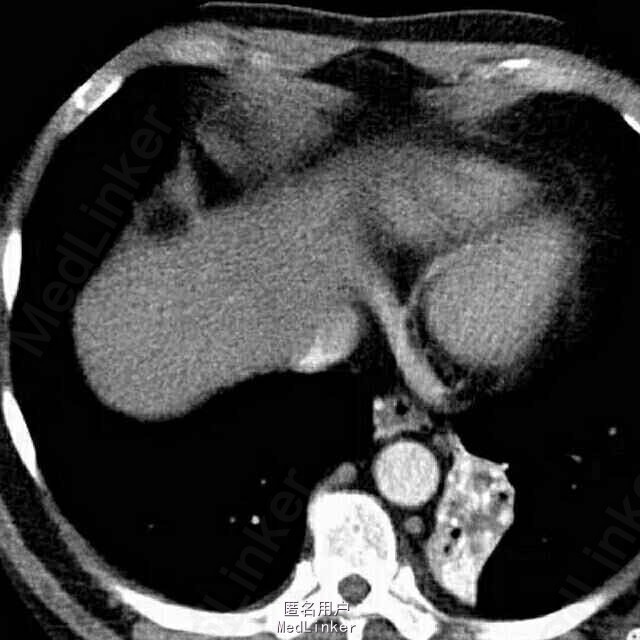

女,50岁。 间断咯血25年余,加重1月,行肺部增强CT。

患者胸部增强CT及血鬼重建影像学表现包括:边界清晰、病变有主动脉分支供血、病变静脉引流入肺静脉。

考虑影像学诊断为:肺隔离症

左肺下叶内前基底段脊柱旁可见斑片影,边界清晰,其内可见支气管气相,平扫密度尚均匀,增强后病变内强化不均匀,可见多发血管影,血管重建示病变由主动脉弓及降主动脉迂曲增粗的小分支供血,可见一直粗大静脉引流入左肺静脉。根据病变部位,供血动脉来源于体循环,静脉引流入肺静脉,此例为典型肺隔离症,已被术后病理所证实。 肺隔离症是一种先天性肺发育畸形,主要特征是部分胚胎肺组织与正常肺组织隔离,病变肺组织的动脉供应由体循环直接分出的动脉分支供应,静脉回流至肺静脉或体循环。尽管其表现多种多样,体动脉向肺组织供血为其最特征表现。常分为叶内型及叶外型2种,最常见为叶内型,多为体动脉单支血管供血,无单独胸膜包裹。叶外型有单独胸膜包裹,多位于膈肌下,由肺或体血管供血,血管较小,多伴有其他先天畸形。本例为叶内型,隔离的肺组织易反复发生感染,出现相关临床表现。 肺炎主要表现为肺实变或不张,常伴有病变周围斑片或淡片影,边界可不清晰,临床症状有助于诊断。 肺癌侵犯病变内及周围血管、支气管,造成支气管闭塞伴远端阻塞性炎症,肺门及纵隔常见肿大淋巴结。 支气管扩张伴感染时可见扩张的支气管,可为管状、串珠样或囊泡状,病变周围感染呈斑片影,边界欠清晰。